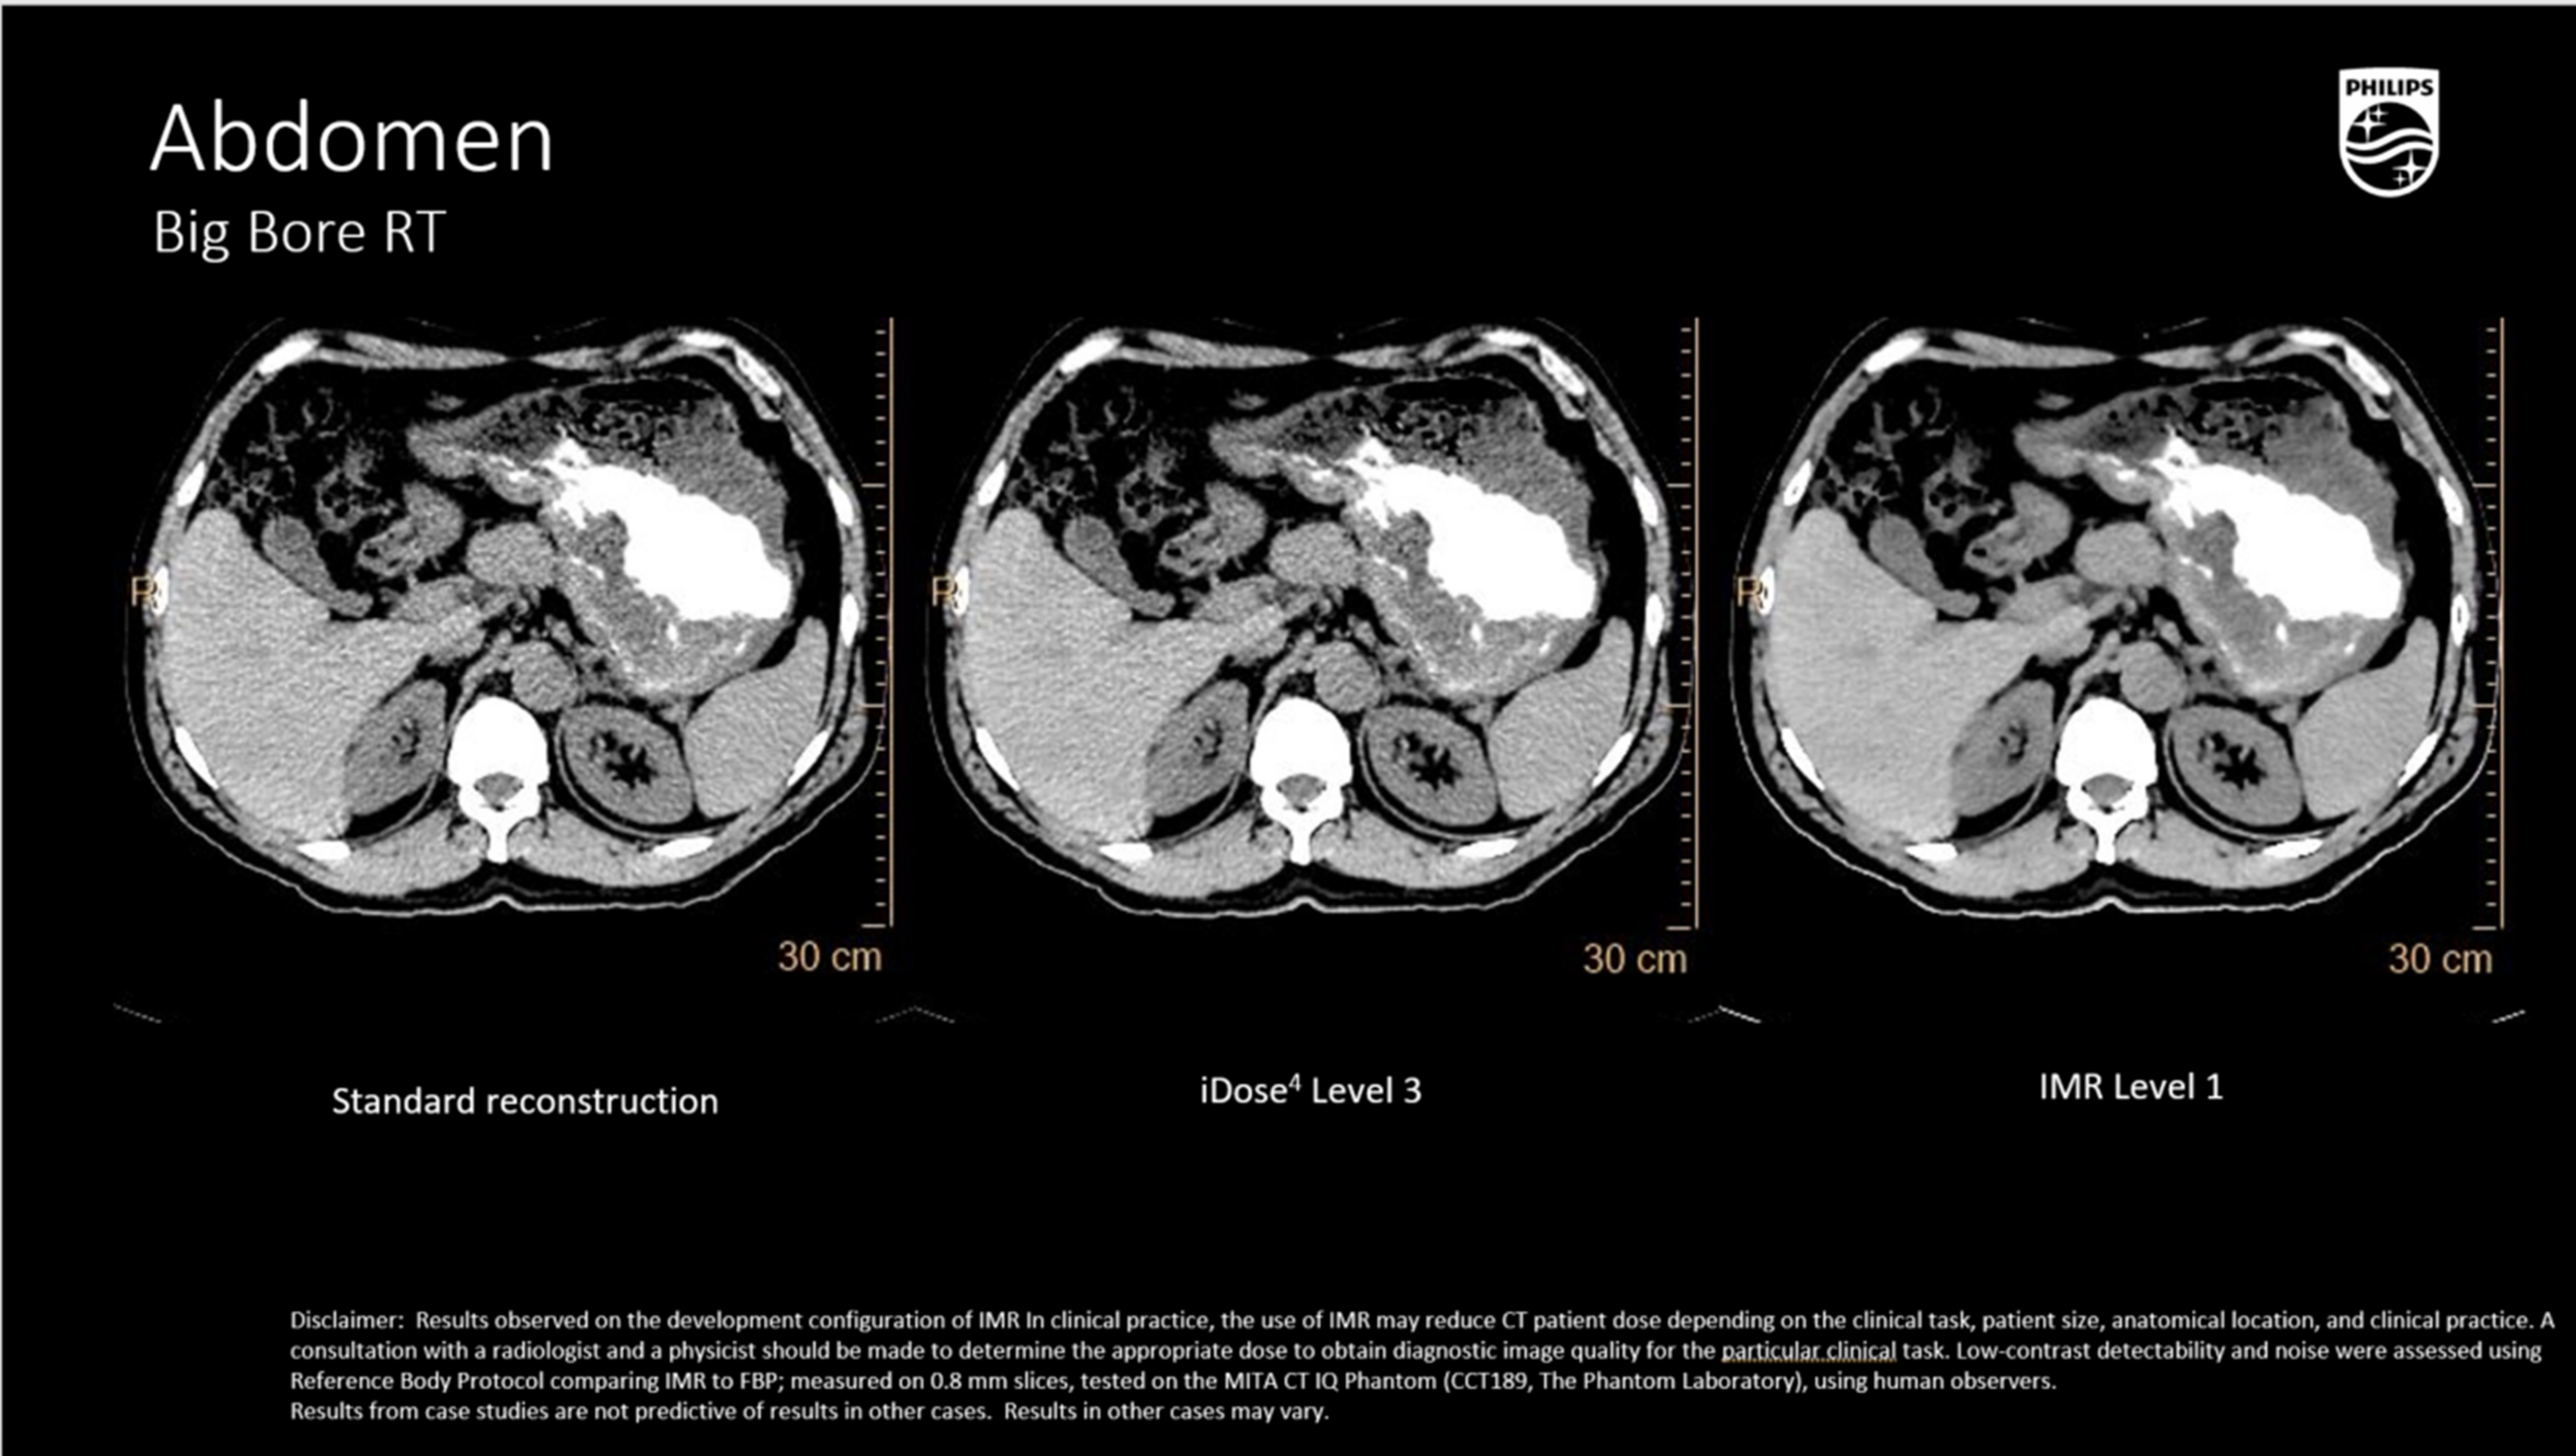

Ключевые технологии визуализации и реконструкции

iDose⁴ (Iterative Dose Reduction Technology)

- Гибридная итеративная реконструкция в проекционном и изображен ческом пространстве повышает качество изображения и устраняет артефакты.

- Повышает контрастно-шумовое соотношение (CNR), снижая лучевую нагрузку на 50–80% при сохранении пространственного разрешения

- Поддержка низкокиловольтных протоколов (100/80 кВ), актуальна при планировании в педиатрии и у кахектических пациентов.